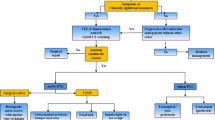

While the majority of patients have subclinical PVL, those with more significant regurgitation can develop hemolysis, severe heart failure, or both. Previously this was managed exclusively by repeat operation or, in cases where repeat surgery was thought to be unsuitable, by medical therapy. In the last two decades, transcatheter closure of PVL has evolved as a viable option for these patients. Indeed, according to the 2017 American College of Cardiology/American Heart Association Focused Guidelines Update for the management of valvular heart disease, transcatheter repair of PVL is a class IIa recommendation in patients with prosthetic heart valves and intractable hemolysis or New York Heart Association (NYHA) class III/IV heart failure who are at high surgical risk and have suitable anatomic features for transcatheter closure in an experienced center [12].

While medical therapy is an important component of symptom management for patients with hemolysis or heart failure due to PVL, there are no known medical therapies to prevent or reverse PVL or its underlying cause [22, 23]. Only surgical repair or transcatheter intervention provides definitive treatment.

For patients with severe heart failure, medical management should mimic the recommendations for patients with symptomatic mitral regurgitation and aortic insufficiency. This includes diuretic therapy for volume overload and afterload reduction in patients with hypertension [22, 23]. Similarly, in patients with endocarditis, appropriate antibiotic therapy should be instituted.

For patients with hemolytic anemia, red blood cell destruction results in accelerated erythropoiesis. As a result, patients should receive folic acid and iron supplementation (either oral or intravenous) [15]. In some cases, hemolytic anemia may be so severe to warrant transfusion, although there is no agreed upon threshold to transfuse to, which is also influenced by the patient comorbidities. In limited retrospective studies, beta-blockers have demonstrated improvement in hemolytic anemia, postulated to occur due to a decrease in red blood cell shear stress [37,38,39]. Similarly, erythropoietin has been used with some success in patients with PVL who were unable to undergo surgical replacement but in small patient series [40].

Surgical replacement

Based on the 2017 AHA/ACC Focused Guidelines Update for the management of valvular heart disease, surgical valve replacement is a class I indication for operable patients with mechanical valves with intractable hemolysis or heart failure due to severe PVL [12]. For many patients, surgical replacement may carry moderate or high operative risk. This is a result of the necessity for a re-do operation and the fact that most patients are typically older with a greater number of comorbidities. Moreover, until recently, the majority of patients who underwent TAVR did so due to their intermediate or higher surgical risk at the time of valve implantation.

Transcatheter repair

For patients with high surgical risk and severe, symptomatic PVL, transcatheter repair carries a class IIa indication according to the 2017 AHA/ACC Focused Guidelines Update for the management of valvular heart disease [12]. Critically, it should be noted that transcatheter repair of PVL is contraindicated in patients with active endocarditis, rocking motion or instability of the prosthesis (i.e., valvular dehiscence) PVL involving > 30% of the sewing ring (relative contraindication) [8].